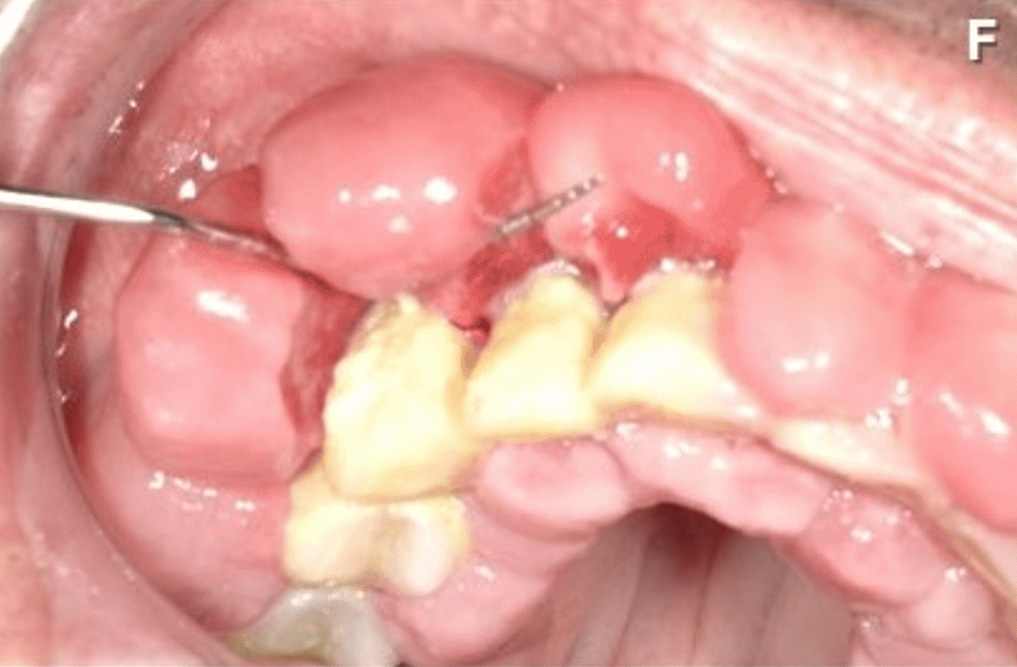

覚醒剤を乱用した61歳の男性の歯茎を撮影した画像。

5年間の覚醒剤使用とホームレス生活により口腔衛生不良があり、歯肉の肥大、疼痛、出血による咀嚼困難で病院へ。